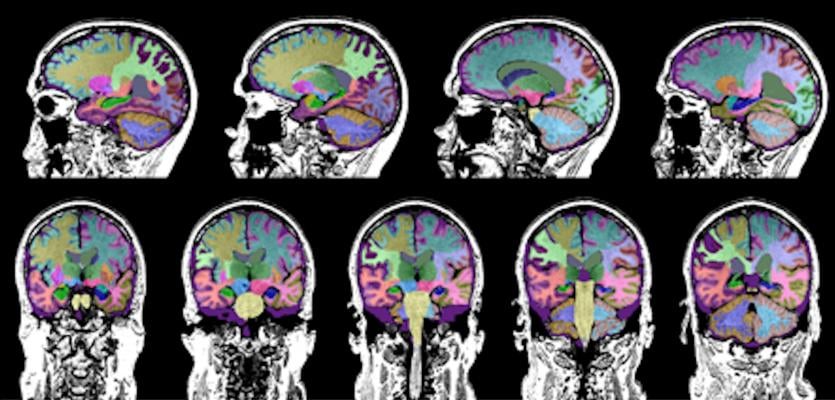

The Neuroreader software program quantifies brain volume in study participants with TBI. Image courtesy of UCLA Health.

“We already knew that MRIs can reveal subtle abnormalities in patients with neurological disorders, such as Alzheimer’s,” said Somayeh Meysami, M.D., lead author and a postdoctoral clinical research fellow in cognitive and behavioral neurology at the David Geffen School of Medicine at UCLA. “The purpose of our study was to evaluate whether MRI also could reveal distinct abnormalities in traumatic brain injury. And, if we could identify such a pattern, it would lead to improved diagnosis of TBI-related memory loss from other causes of dementia.”

Using a software program to analyze the MRI scans, the study revealed that TBI caused the most damage to a brain region known as the ventral diencephalon, with the least amount of atrophy occurring in the hippocampus, said study author Cyrus Raji, M.D., an assistant professor of radiology at Washington University in St. Louis. The ventral diencephalon is associated with learning and emotions, whereas the hippocampus is involved in memory and emotions. The hippocampus also is the region of the brain that is most impacted by Alzheimer’s disease.

“The method we used to measure brain volumes in these individuals is useful because it can be applied on the same type of MRI scans we obtain in the clinic with no special type of imaging required,” Raji said.